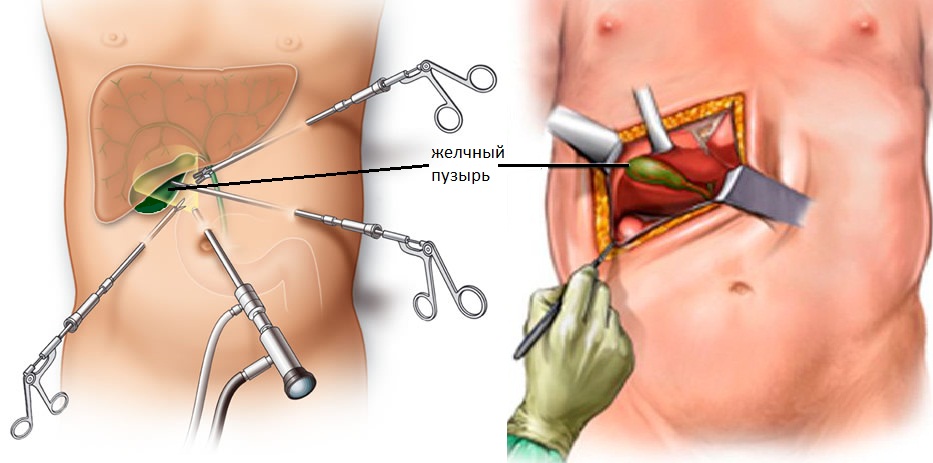

Современные методы лапаротомии и миомэктомии